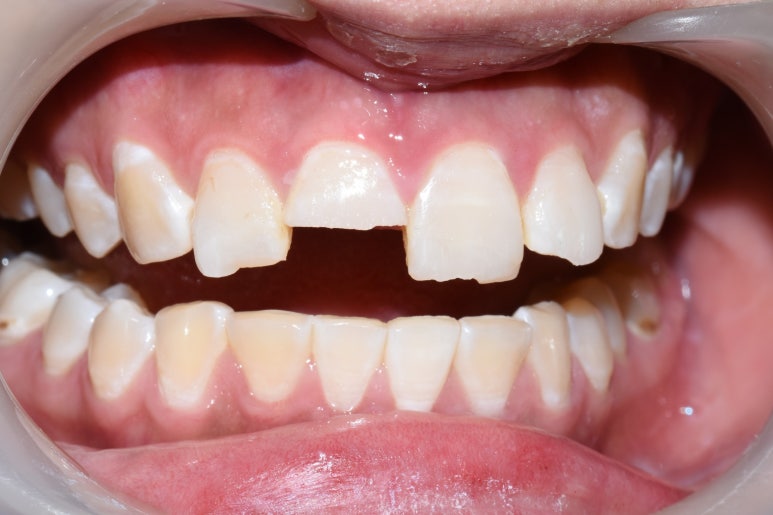

저희 치과의 경우도 이 치아 하나는 너무 많이 깨져서 파절선이 잇몸속에 있는 이 치아 하나는

발치하고 임플란트가 가장 첫번째 옵션이라고 설명 드렸지만

환자분이 임플란트는 하고 싶지 않았기 때문에

다른 치료를 해보고 싶다고 하셔서 일단 깨지면서 치아신경이 노출된 치아라서 신경치료부터 시작하면서 예후를 지켜보기로 하였습니다.